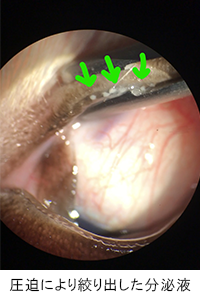

スリットランプ検査にて、マイボーム腺のつまりを確認。圧迫により濁った分泌液を絞り出しました。

| マイボーム腺機能不全と診断。マイボーム腺が目詰まりを起こし、ドライアイ状態になっていました。治療としては眼瞼マッサージや温罨法、ヒアルロン酸点眼などを行います。 完治が目標ではなく、良好な状態を維持することが大切なので、自宅でのケアが大切になります。 |